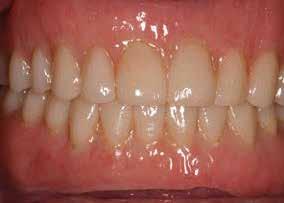

Bevezetés

Az azonnali, implantátumokkal megtámasztott teljes íves fogpótlások jól bevált, és egyre inkább elfogadott kezelési módot képviselnek a teljesen fogatlan betegek rehabilitációjában.1,2 Az ilyen típusú helyreállítások esetében átlagosan 5 éves követési időszakban 98%os túlélési arányról számoltak be.3 Az alsó állkapocs kedvező csontminőségnek és anatómiának köszönhetően az azonnali teljes ívek helyreállítása még nagyobb sikerarányt mutatott.4 A digitális technológiák, mint például a sablonnal végzett implantátumbeültetés és a számítógéppel segített protézistervezés és gyártás, képesek megkönnyíteni a diagnózist, a kezelés megtervezését és jelentősen javítják a sebészeti beavatkozásokat, ezáltal kiszámíthatóbb és hatékonyabb kezelést biztosítanak.5,6 Különösen a bonyolult sebészeti eljárások – mint például a teljes ív rekonstrukciója – jelentős mértékben profitálhatnak ezekből az előnyökből, amelyek csökkenthetik a kezelés idejét és az invazivitást a beteg számára.5,7

A digitális technológiákhoz való hozzáférést az anyagi és időkorlátok akadályozhatják, valamint az ilyen technológiákhoz kapcsolódó meredek tanulási görbe.8,9 A közelmúltban a digitális munkafolyamatok elérhetővé váltak egy kihelyezett szolgáltatás részeként: Smile in a Box (Straumann). Ez segíthet a hagyományos munkafolyamatokat használó szakembereknek, hogy könnyen élvezhessék a digitális technológiák előnyeit anélkül, hogy először le kellene küzdeniük az első hozzáféréssel járó akadályokat. Ez az esettanulmány egy hagyományos teljes fogsor sikeres azonnali átalakítását írja le azonnali teljes ívű restaurációvá a Smile in a Box által biztosított kiszervezett, teljesen digitális munkafolyamat alkalmazásával. A Straumann Pro Arch protokoll alkalmazása a Smile in a Box funkcióval kombinálva lehetővé tette számunkra, hogy könnyen hozzáférhessünk egy teljesen digitális munkafolyamathoz, amely hatékonyan integrálható a hagyományos protetikai munkafolyamatunkba, továbbá rendkívül kielégítő klinikai eredményt biztosít.

Klinikánkon egy teljesen fogatlan, hagyományos akrilát fogpótlással helyreállított 65 éves férfi beteg jelentkezett, aki nem kielégítő alsó fogsorretencióra és az azzal járó problémákra panaszkodott, beleértve a kifejezetten az alsó fogsorához kapcsolódó gyenge beszéd és rágásfunkciót. A klinikai vizsgálat gömbölyűtől a késhegyig terjedő mandibulagerinc formát és megfelelő vertikális, de nem megfelelő vízszintes csontmennyiséget állapított meg, különösen a hátsó területen (1. ábra) 10

témás vagy lokális kockázati tényezőket vagy ellenjavallatokat, amelyek kizárták volna a pácienst az implantációs kezelésből. A különböző kezelési lehetőségekről, azok előnyeiről és korlátairól szóló alapos megbeszélést követően a páciens egy implantátumokon megtámasztott alsó fogsort kombinálva egy új, hagyományos felső teljes kivehető fogpótlást részesített előnyben.

A hagyományos teljes kivehető fogpótlási technikákkal a kezelési stratégia a felső és alsó állcsont kapcsolatának és az okkluzális vertikális dimenzió és a fog helyzetének meghatározását foglalta magában, majd az alsó rögzített restauráció előállításához ezeket használták fel referenciákként (3. ábra) 11